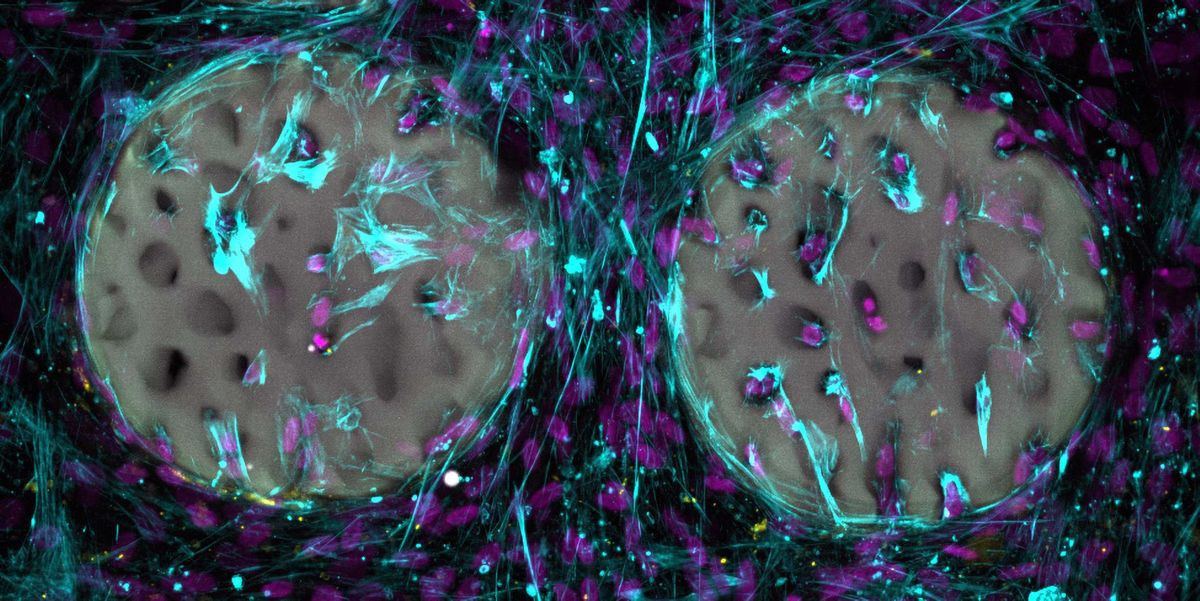

Οι προκλινικές δοκιμές, όπως περιγράφονται στη μελέτη, απέδειξαν την υψηλή βιοσυμβατότητα του υλικού. Όταν τοποθετήθηκαν οστεοβλάστες (τα κύτταρα που συνθέτουν το οστό) πάνω στην τρισδιάστατη δομή του υδροτζέλ, τα κύτταρα όχι μόνο επιβίωσαν, αλλά διείσδυσαν βαθιά στους πόρους του υλικού. Ξεκίνησαν άμεσα την παραγωγή κολλαγόνου, επιβεβαιώνοντας ότι το περιβάλλον είναι ιδανικό για την αναγέννηση των ιστών. Καθώς το σώμα χτίζει το δικό του οστό, τα ένζυμα του οργανισμού διασπούν φυσιολογικά το πολυμερές δίκτυο του υδροτζέλ, το οποίο αποβάλλεται χωρίς να προκαλεί τοξικότητα.